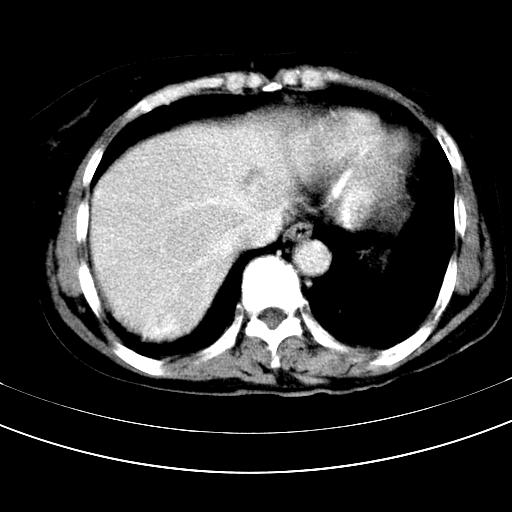

标题: CT12767:肝脏病变请会诊

胃内见充盈缺损,建议行胃镜病理检查,如果胃内无占位,则肝内考虑左叶、尾叶为包膜型肝癌,如有则考虑为转移瘤

胃内的充盈缺损,当时让患者俯卧位在扫描一下就 好了,当然最好是增强扫描,肝脏的病灶平扫很难定性,可以考虑是肝癌·血管瘤·转移瘤!

胃内的充盈缺损因胃壁不厚,我个人考虑为胃内残留物。肝左叶及尾叶病灶,我首先考虑血管瘤,其次为肝癌。(尾叶的更低密度区太规整)

肝脏左叶和尾叶均见略低密度影,尾叶病变内见坏死?其边界清晰,形态规整1血管瘤,2肝癌待排

1.肝左叶及尾叶占位建议增强2.肝硬化